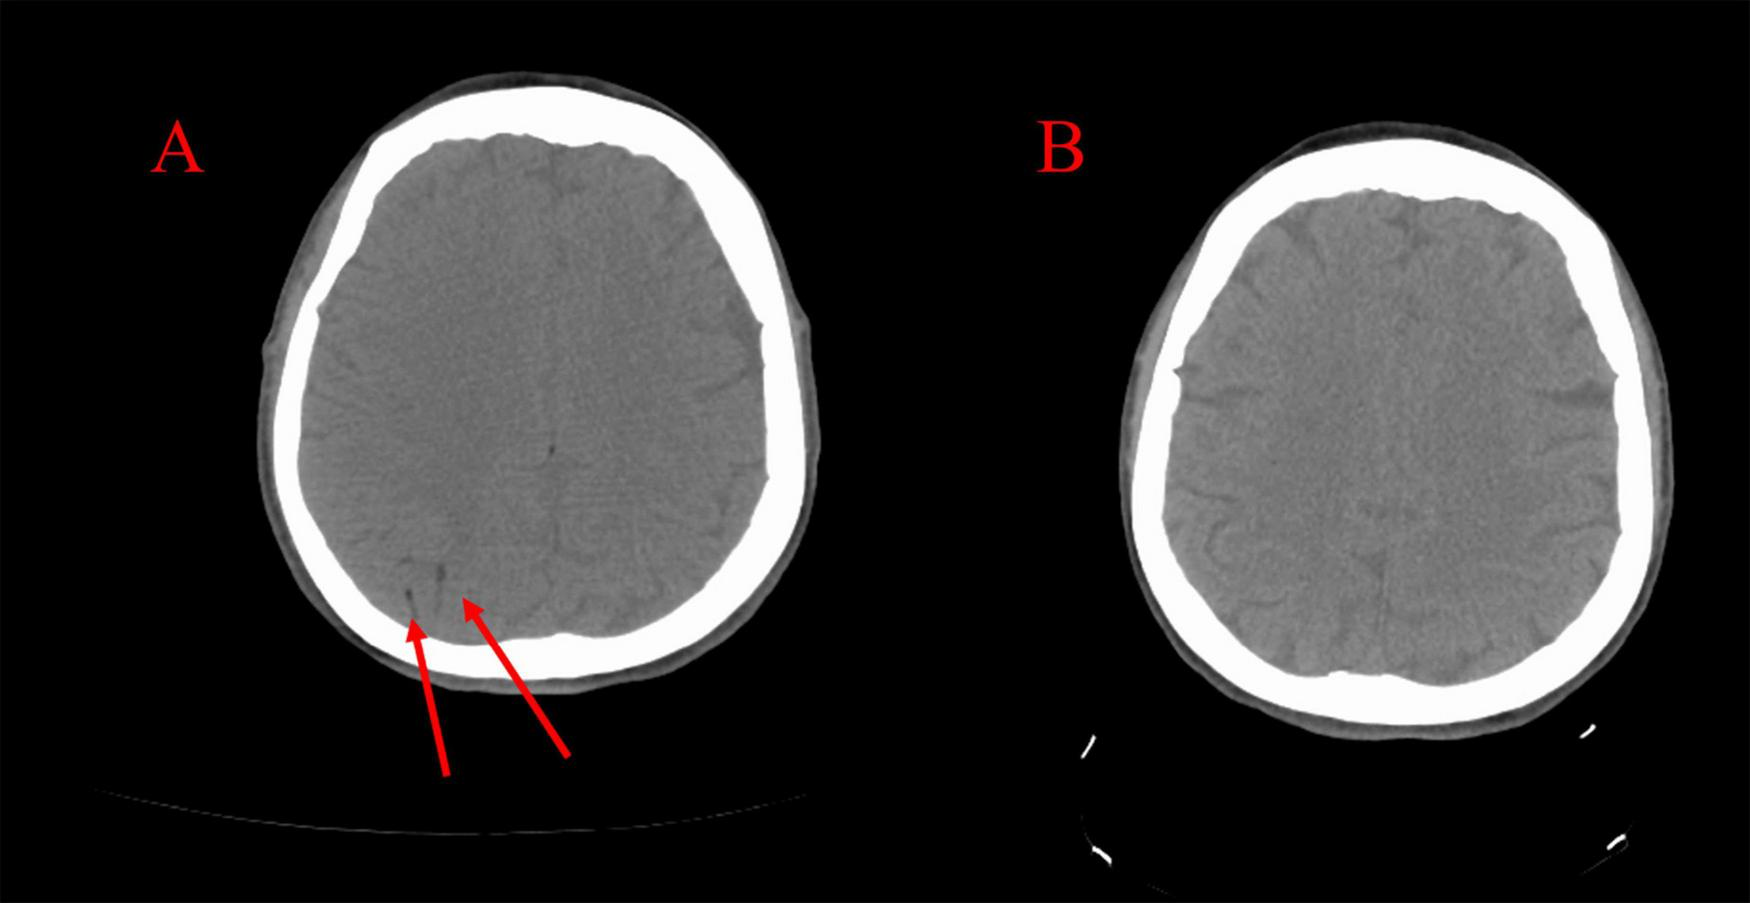

FIGURE 2

(A) CT scan taken immediately following the stroke demonstrating right-sided cerebral arterial gas embolism. (B) CT scan taken following hyperbaric oxygen therapy demonstrating resolution.

Upon arrival at the accepting hospital, the patient had maintained a GCS of 10 and was still protecting her airway. A critical care physician was consulted and did not recommend endotracheal intubation. The patient underwent repeat CT scanning of the head, which showed resolution of the CAGE (Figure 2B). On the evening of the biopsy, she was noted to have a flexor response of the upper extremities and lower extremities with hyperreflexia of the brachioradialis, patellar, and Achilles tendons, and four-beat ankle clonus. Her GCS score measured a total of 9 (E4, V2, M3) indicating a fluctuating level of consciousness, yet she continued to protect her airway. The laboratory data were within normal limits. A repeat CT scan with angiography of the head and neck revealed no further visible bubbles in the brain, and all vessels appear patent.